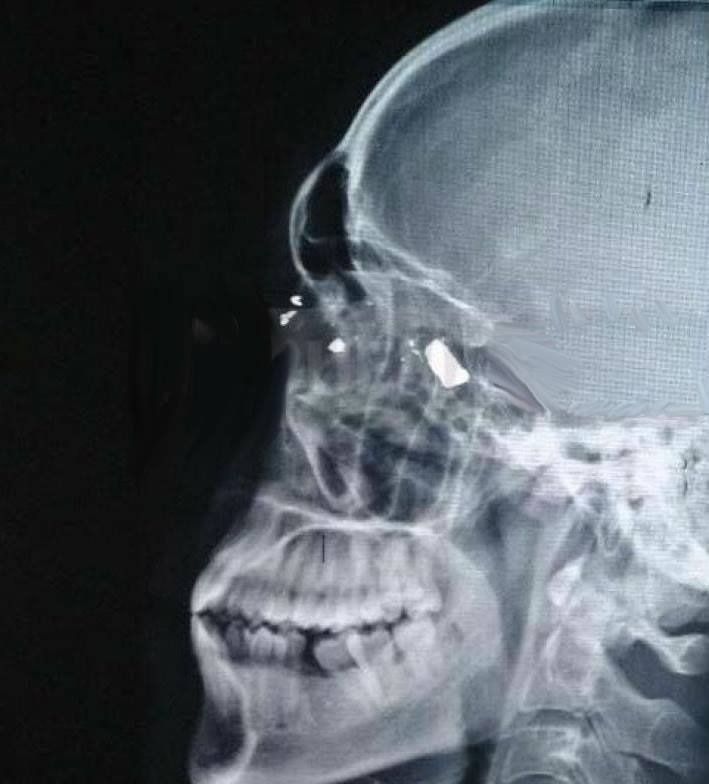

Según los voceros, la víctima fue atendida pero, para sorpresa de todos, recibió el alta médica apenas un día después del hecho ya que la bala no afectó áreas vitales. No obstante, se indicó que el plomo continúa alojado en su cráneo, por lo que deberá ser evaluado en las próximas horas.